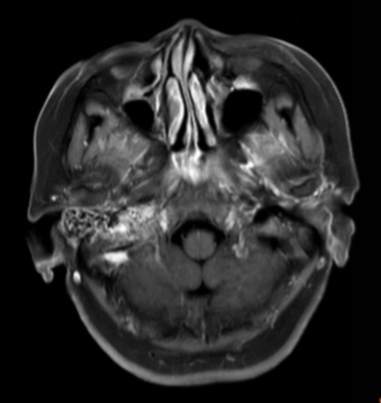

(2023-05-15 10:00,本院)行磁共振(颅脑)检查提示:右侧乳突区异常信号,考虑恶性、软骨来源肿瘤,软骨肉瘤可能性大。(集体讨论意见);脑内散在多发缺血灶。

(2023-05-12 10:15,本院)行CT(颅脑)检查提示:右侧颞骨广泛骨质破坏,伴巨大软组织肿块,性质待定,考虑肿瘤性病变,颈静脉球瘤?软骨源性肿瘤?请结合临床及病理进一步明确。